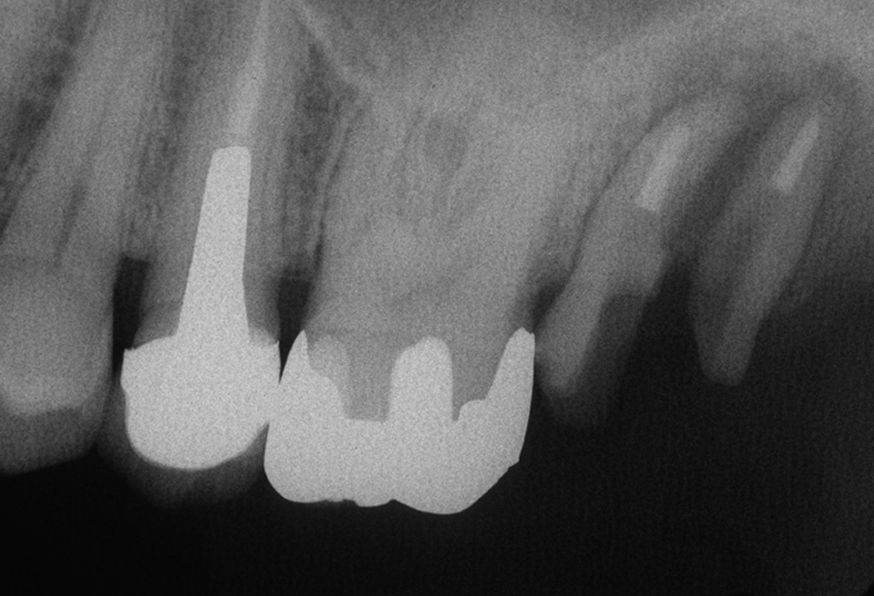

図8 根管治療終了・口蓋根抜歯終了時レントゲン写真

残すことが出来た2本の歯根は状態は悪くありませんが、歯を支える骨のダメージは大きいため慎重な治療が必要になります